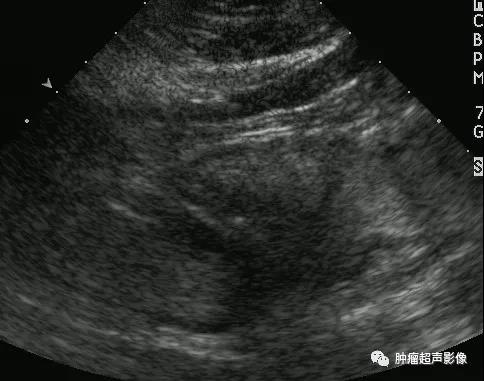

超声表现:一般呈低回声(少部分为高回声,胃血管球瘤一般都呈高回声,类似肝脏血管瘤表现),多为类圆形或椭圆形,边界清,较大肿瘤可显示其对指骨的侵蚀,内部及周边血流丰富,典型的呈花环状或小火球样,频谱呈低速低阻。

胃血管球瘤呈类圆形,边界清的高回声,类似肝血管瘤的表现